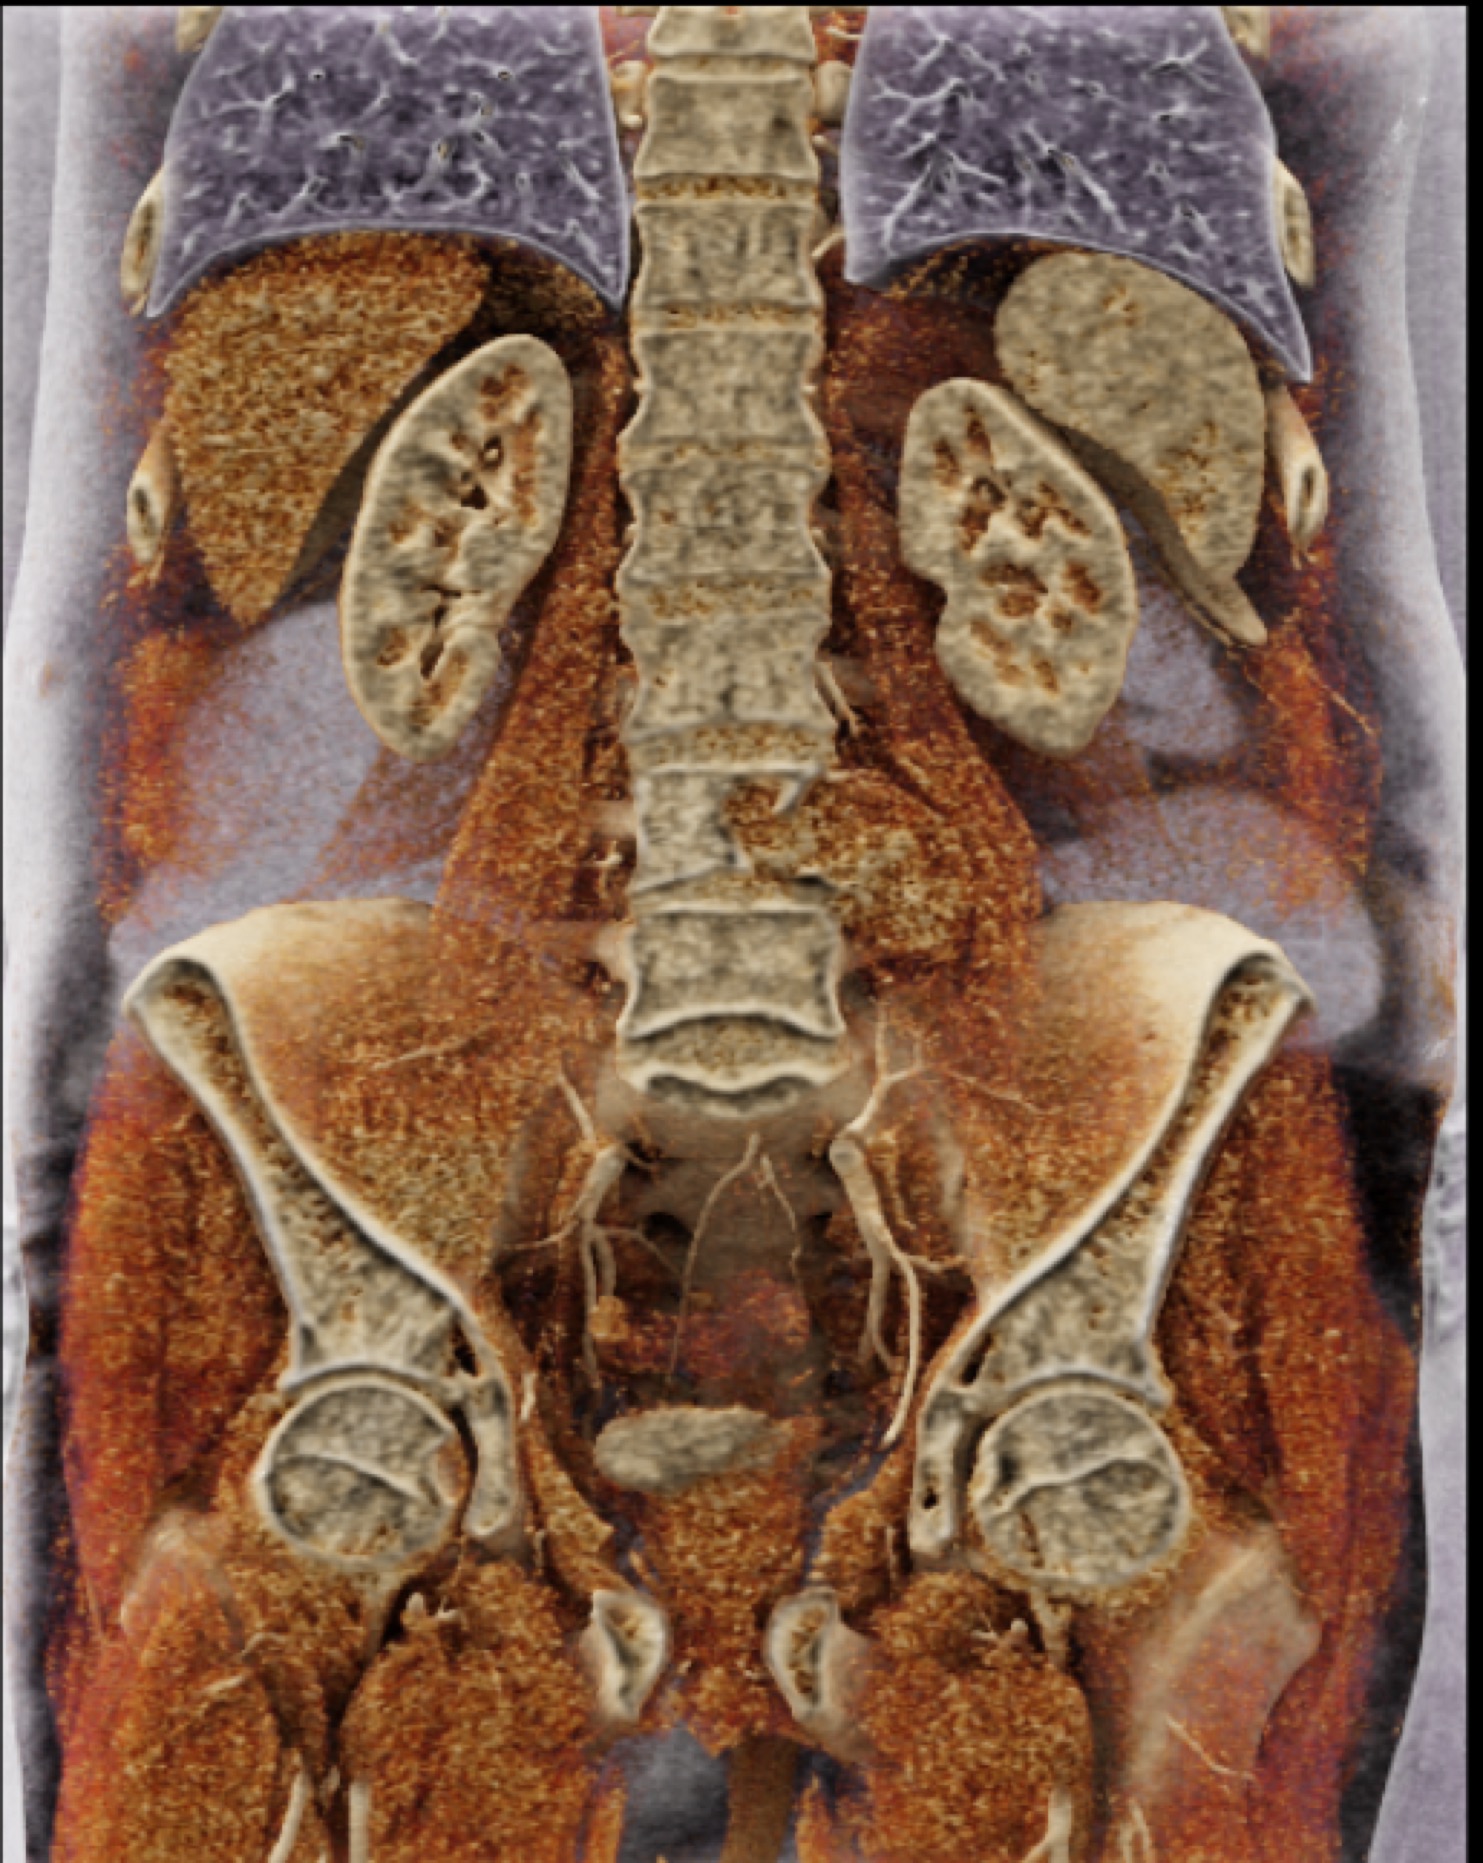

2) The differential diagnosis in this case includes?

FMD (fibromuscular dysplasia)

SAM (systemic arterial mediolysis)

Takayasu’s aortitis

all of the above